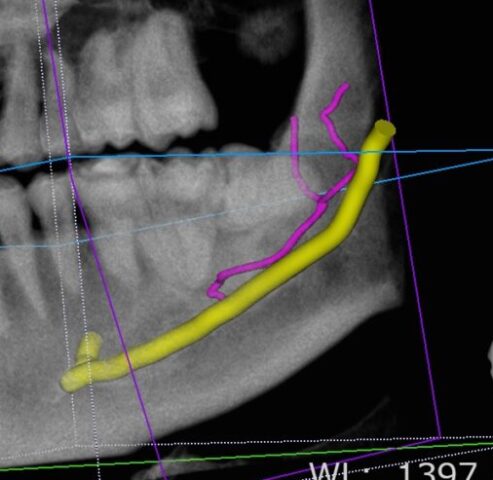

CT画像では、

途中で枝分かれしている

神経が歯のすぐ近くを走行している

ことが確認できました。

黄色が神経(下歯槽管)、ピンクが神経(下歯槽管)から分岐です。